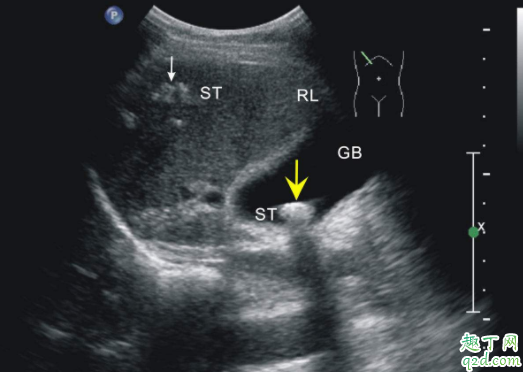

羊水的多少,一般用B型超聲診斷法,一啊不能妊娠期28-40周,最大羊水池徑線穩(wěn)定在5.1±2.1cm的范圍。AFD≤2cm則為羊水過少,≤1cm為嚴(yán)重羊水過少。